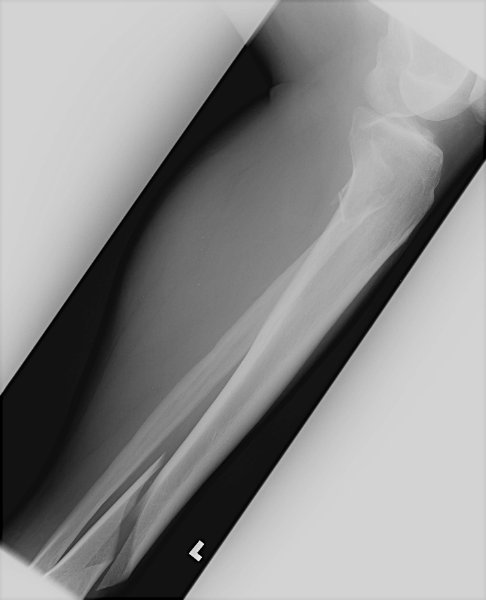

Return to Tibial Shaft Fracture